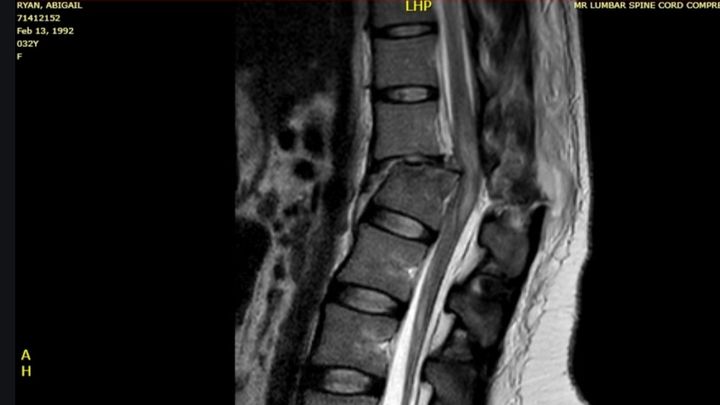

After arriving at the trauma bay and being asked a million and one questions by doctors in order for them to assess me, I'm rushed into surgery for a spinal fusion. I wake up and still cannot move my lower half. Doctors tell me I shattered my L1 and even though it was an incomplete injury, they don't know how much I'll get back and if I will ever walk again. The rest is history. I spent over a month in the hospital and fought like hell in therapy to make advances, and that I did. I started to get some motion and sensation in my legs back. I even got to the point of being able to stand up and push my legs to make steps with a bilateral walker and some assistance. Now there isn't a question in my mind of if I will walk again, it's a matter of when. I lost a lot that day, but I gained a fire inside of me I had never felt before. There's no giving up or quitting. There's only the moment I visit all the staff that took care of me, and I walk through the same doors I rolled out of a wheelchair in.